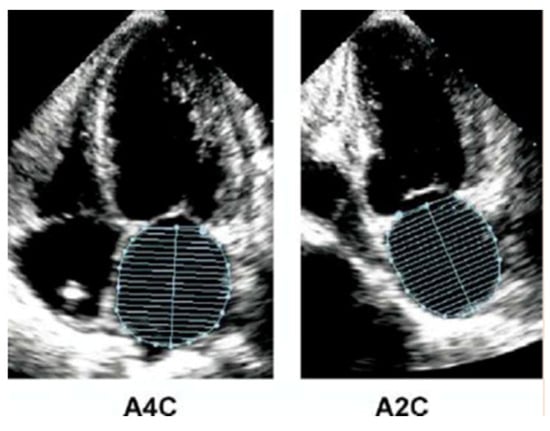

2.2.1. Atrial Dimension